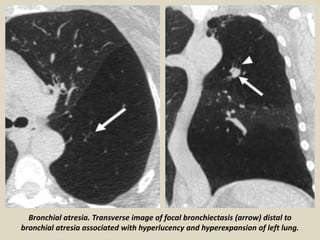

Bronchial Atresia

The most common cause of

congenital focal bronchiectasis

is bronchial atresia,

characterized by obliteration

of a bronchus with distal

bronchiectasis, mucoid

impaction, and air trapping

that is most commonly seen in

the left upper lobe. In this rare

lesion, the bronchial tree

peripheral to the point of

obliteration is patent and the

lung parenchyma is

overinflated because of

collateral air drift.

Bronchial atresia. Transverse image of focal bronchiectasis (arrow) distal to

bronchial atresia associated with hyperlucency and hyperexpansion of left lung.